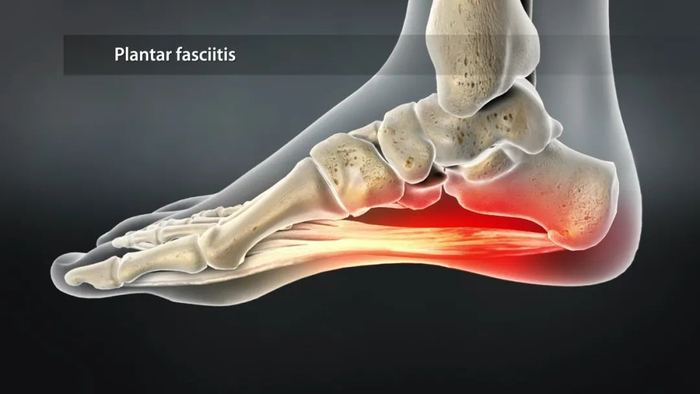

人的脚是由众多足骨所构成的一个拱形构架,这种拱形结构连同脚底多层软组织(脂肪垫、筋膜)构成了足弓。

足弓可以发挥很好地适应地面,缓冲足着地时的撞击力、避免足底血管神经免受压迫等作用。

足底筋膜就是位于足底的软组织,它起自脚跟处的跟骨,向前止于脚趾,由于脚趾头有五个,足底筋膜向前分叉为五束,足底筋膜的主要功能是缓冲,同时也协助维持足弓。

在跑步时脚离地过程中,脚趾头特别是大脚趾也会用力,此时脚趾背屈时相当于在足底筋膜远端产生张力,坚硬的足底筋膜就会被动牵拉跟骨,产生“卷扬机效应”,使足弓抬高。

离地阶段跖趾关节会产生明显的背屈运动对足底筋膜产生牵拉

结果发现,由于鞋头跷度的存在,导致在脚趾离地过程中,跖趾关节主动背屈角度变小,但并没有因此减少足底刚度,也就意味着在更小的脚趾活动中,足底筋膜产生了更大的张力;

同时这种更大张力产生本身也跟鞋头跷度导致的静止状态下,足底筋膜本身就存在一定张力,并随着跖趾关节背屈,张力进一步累加有关。

在着地最后阶段,大脚趾会产生明显的背屈运动,此时跖趾关节中心会受到地面反作用力和足底肌肉拉力两个作用力,这两个力要保持相对平衡,由于足底筋膜的张力增加,事实上就可以减少足底肌肉的用力。